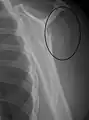

Proximal humerus fracture

A transverse fracture of the humerus shaft